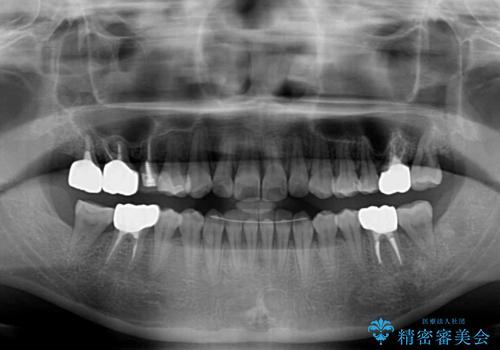

- 捻れた前歯と目立つ銀歯を気にして来院された患者様です。

歯列不正は軽微であったため、インビザライン・ライトにて改善することとしました。

左下大臼歯は根管治療が必要であったため、矯正治療前に根管治療を行い、その後矯正治療を行うこととしました。

矯正治療後には期にある銀歯を全てセラミッククラウンなどで補綴治療することとしました。